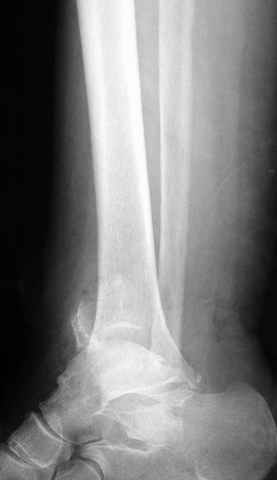

Pilon fracture:

-Появляется ориентир и остов, на чем можно строить восстановление, почему сперва малоберцовую, впервые обьяснили и описали (Pylon type and Ankle fractures) в середине 50х Rienau и Gay.

Восстановливая длину и ротацию малоберцовой кости, затем относительно легче произвести реставрацию остальных элементов перелома дистального эпиметафиза болшеберцовой кости.

конец малоберцевой кости, к нему прикрепляется латеральный суставной фрагмент дистального эпиметафиза большеберцовой кости (как на снимке)

и таранная кость, которые при репозиции малоберцовой кости репонируются автоматически.

Дистракция в аппарате или на вытяжение результат - лигаментотаксис, посмотреть бы, как сегодня расположены отломки.